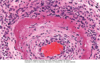

What type of necrosis? Cause?

Fibrinoid necrosis

Often in blood vessels in response to immune-mediated or hypertensive injury

Preserved architecutre

get fibrin and neutrophils